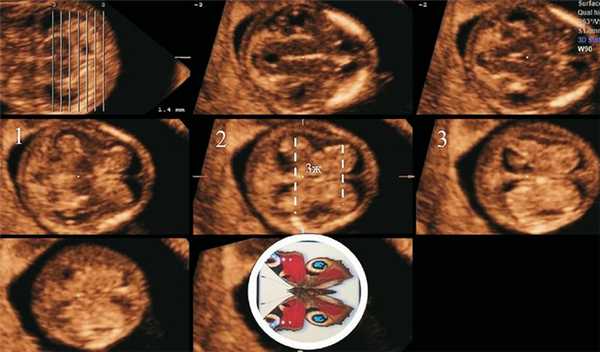

В группу исследования было включено 22 плода с ОДП, диагностированным в I триместре беременности. При этом в 13 случаях это было первичное выявление, а в остальных 9 случаях пациентки с подозрением на патологию позвоночника плода были направлены в наш кабинет для уточнения диагноза.

На момент исследования КТР составил в среднем 61,4 мм (в пределах 46,3-80,6 мм). На рис. 4 представлены полученные картины СС на стандартном аксиальном срезе на уровне крыши III желудочка во всех исследованных случаях. Отдельно показаны 5 случаев проспективной оценки картины СС боковых желудочков при ОДП плода. Данные КТР и БПР головы плода приведены соответственно для каждого случая на этом же рисунке.

У всех плодов с ОДП при эхографии структур головного мозга было отмечено отсутствие типичной картины «бабочки» СС независимо от уровня их исследования.

Объединяющими характеристиками картины СС при этом были

- Уплощенный (или с некоторой выпуклостью) латеральный контур сплетений с отсутствием характерной для «бабочки» талии посередине.

- Практически одинаковое расстояние между затылочными и лобными порциями.

- Отсутствие картины крыши III желудочка.

По аналогии сравнения нормальной картины СС с «бабочкой» полученные нами характеристики картины СС у плодов с ОДП вызвали у нас ассоциацию с различной формой хитиновых оболочек «тараканов» (см. рис. 4).

Рис. 4. Отображена эхографическая картина аксиального среза СС на уровне крыши III желудочка у всех плодов с ОДП, диагностированными нами в 11-14 нед беременности.

Приведена аналогия с хитиновыми оболочками «тараканов». В последнем ряду показаны случаи проспективной оценки СС при ОДП. В каждом случае приведены копчико-теменной и бипариетальный размеры плода соответственно.

Как видно на обзорном рис. 4, результаты нашей работы показали, что площадь СС боковых желудочков относительно общей площади головного мозга является различной - у 16 плодов они практически заполняют весь объем черепа, у остальных являются уменьшенными.

Другой причиной различия результатов оценки площади СС может быть получение аксиальных срезов головного мозга на различных уровнях (рис. 5). Так, мы оценивали СС на уровне крыши III желудочка с коррекцией вертикальности среднесагиттального среза, так как только при таком подходе возможно получение признака «бабочки», тогда как в работе R. Chaoui и соавт. [8] для оценки СС использован трансвентрикулярный срез. Как видно на рис. 5, на трансвентрикулярном срезе можно получить различную картину СС в зависимости от проведения исследования на строго аксиальном срезе или с выведением максимального продольного размера боковых желудочков. Эта ситуация может быть связана с тем, что в I триместре нет описанных четких ориентиров для стандартизации аксиального трансвентрикулярного среза [1].

Рис. 5. Отображена различная картина СС боковых желудочков у плода с ОДП в зависимости от уровня и ориентации исследования.

1 - аксиальный срез на уровне крыши III желудочка при вертикальной ориентации; 2 - аксиальный трансвентрикулярный срез при вертикальной ориентации; 3 - косой трансвентрикулярный срез (наклон головы кпереди примерно до 30°) по максимально продольному размеру СС.